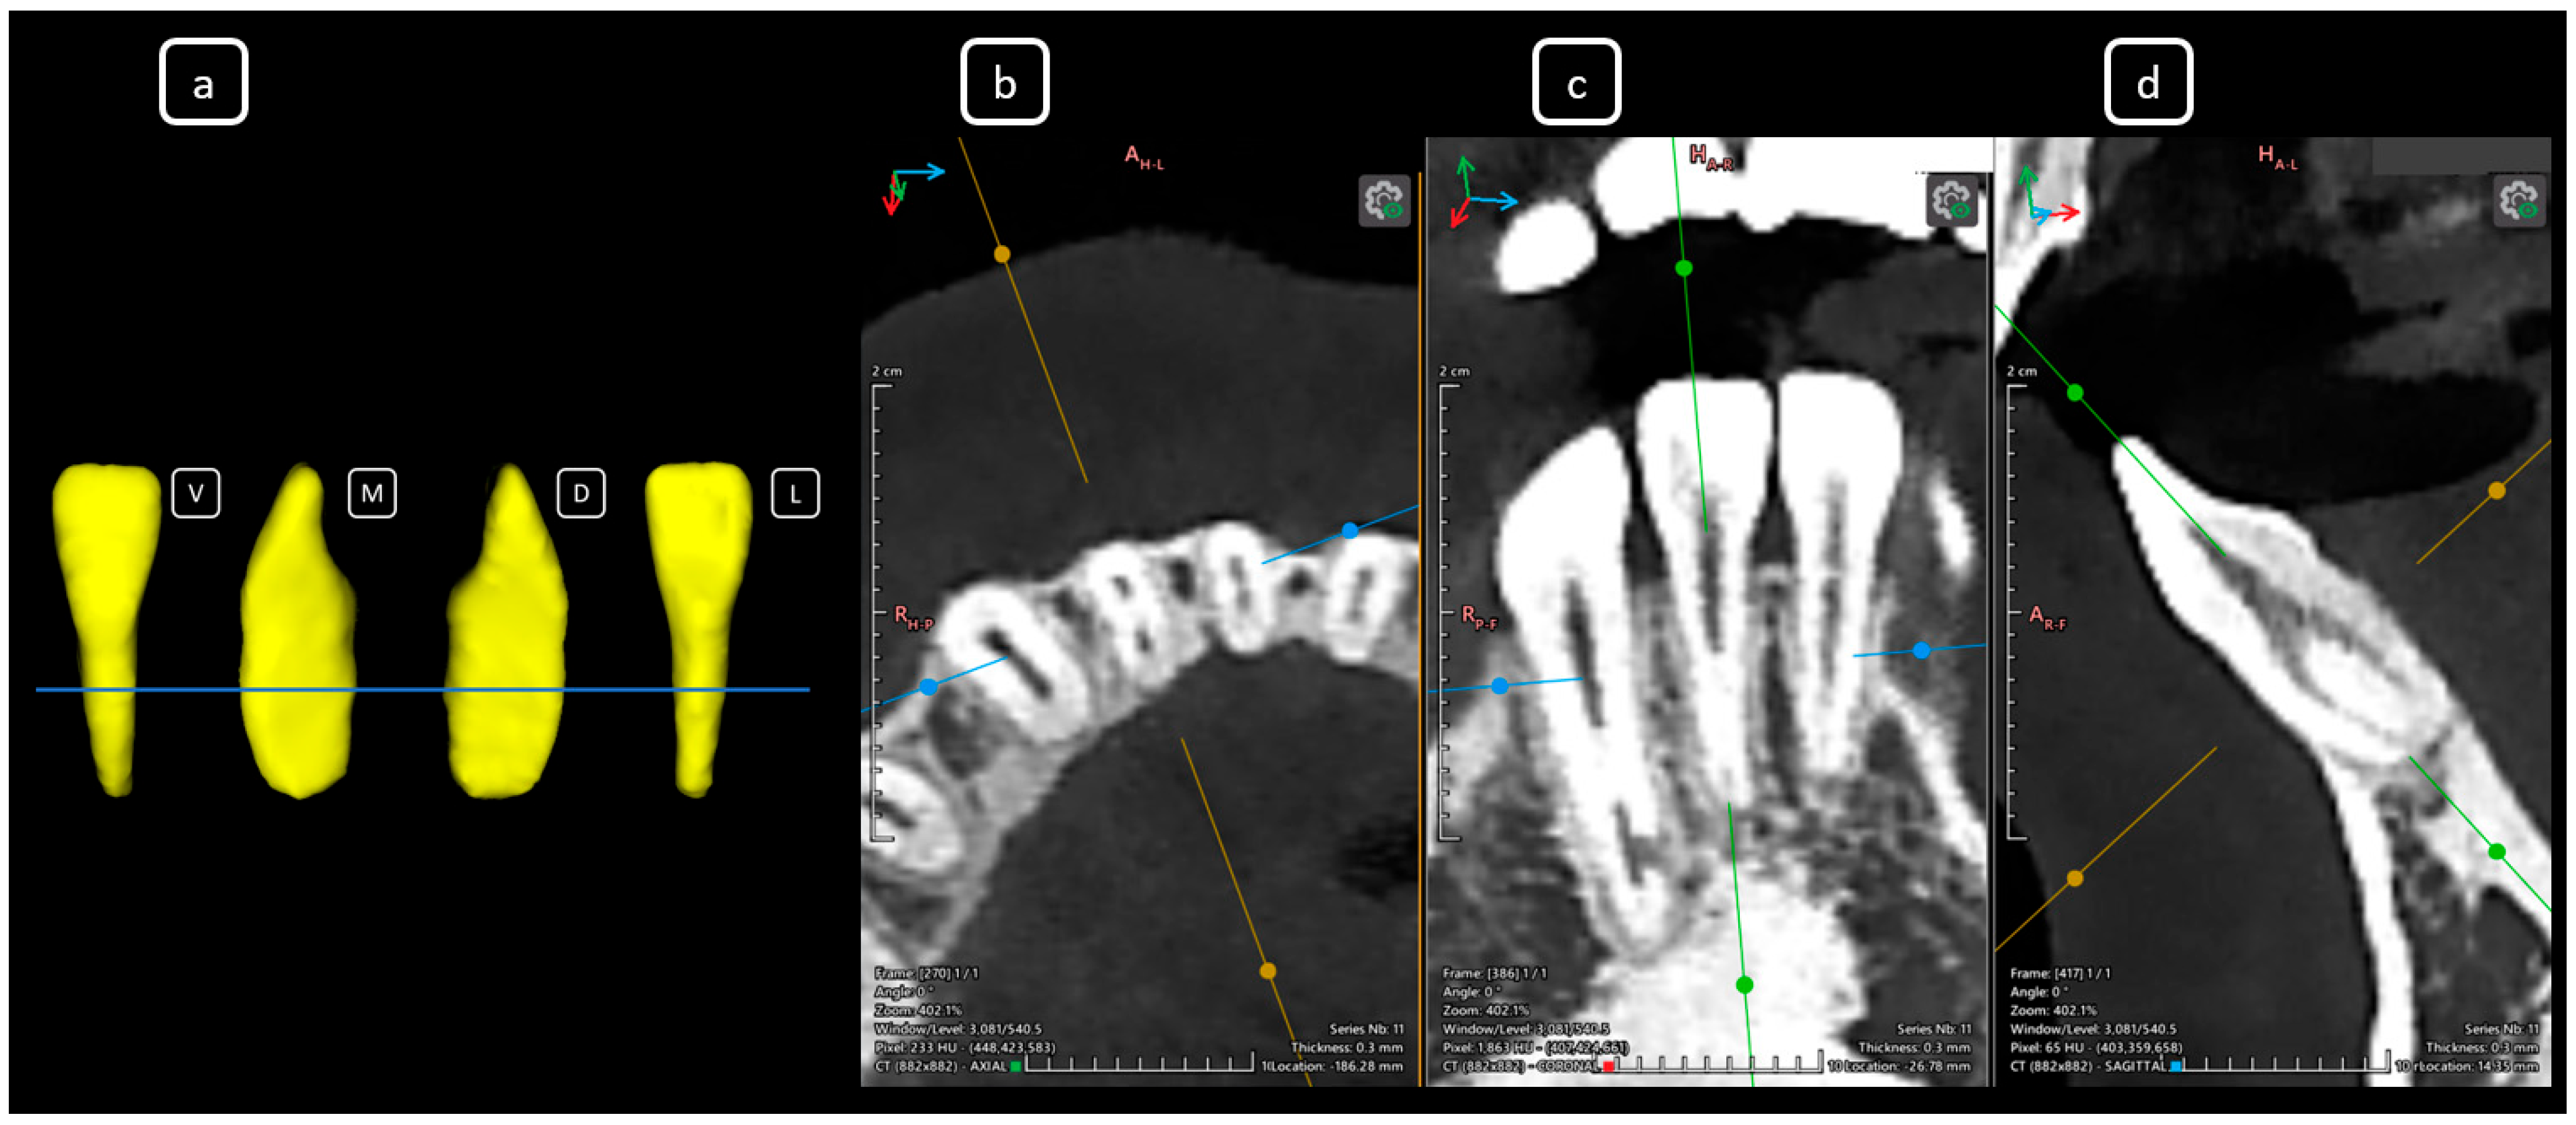

Imaging Findings of Clinical Significance in Endodontics During Cone Beam Computed Tomography Scanning of the Upper Airway—The Anterior, Bilateral, C-Shaped, Dual of Mandibular Root Canals: A Brief Case Report

García-Torres, E.; Guerrero-Falcón, D.L.G.; Bojórquez-Armenta, H.A.; Almeda-Ojeda, O.E.; Barajas-Pérez, V.H.; Solís-Martínez, L.J. Imaging Findings of Clinical Significance in Endodontics During Cone Beam Computed Tomography Scanning of the Upper Airway—The Anterior, Bilateral, C-Shaped, Dual of Mandibular Root Canals: A Brief Case Report. Diagnostics 2025, 15, 3157. https://doi.org/10.3390/diagnostics15243157